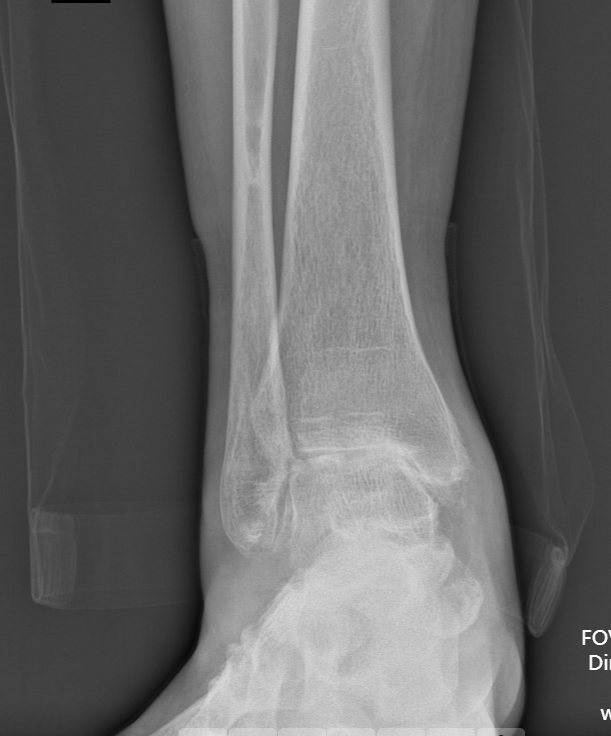

第一台手术的患者是位75岁的叔叔,被“脚脖子”痛缠了4年,疼得越来越厉害,病情已经到了严重阶段。

术前踝关节侧位X线

武勇主任团队给他做了3D打印导板辅助下人工全踝关节置换术。

这种手术适合踝关节病严重的患者,通过替换病变的关节结构,能帮着缓解疼痛、恢复关节活动,让老人日常走路更自在些。